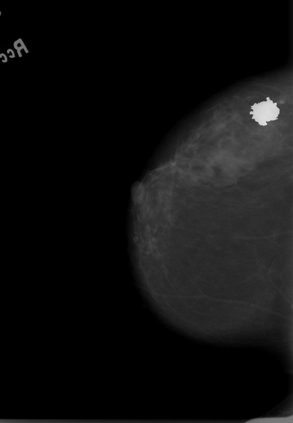

Breast cancer is the most widespread neoplasm among women and early detection of this disease is critical. Deep learning techniques have become of great interest to improve diagnostic performance. Nonetheless, discriminating between malignant and benign masses from whole mammograms remains challenging due to them being almost identical to an untrained eye and the region of interest (ROI) occupying a minuscule portion of the entire image. In this paper, we propose a framework, parameterized hypercomplex attention maps (PHAM), to overcome these problems. Specifically, we deploy an augmentation step based on computing attention maps. Then, the attention maps are used to condition the classification step by constructing a multi-dimensional input comprised of the original breast cancer image and the corresponding attention map. In this step, a parameterized hypercomplex neural network (PHNN) is employed to perform breast cancer classification. The framework offers two main advantages. First, attention maps provide critical information regarding the ROI and allow the neural model to concentrate on it. Second, the hypercomplex architecture has the ability to model local relations between input dimensions thanks to hypercomplex algebra rules, thus properly exploiting the information provided by the attention map. We demonstrate the efficacy of the proposed framework on both mammography images as well as histopathological ones, surpassing attention-based state-of-the-art networks and the real-valued counterpart of our method. The code of our work is available at https://github.com/elelo22/AttentionBCS.